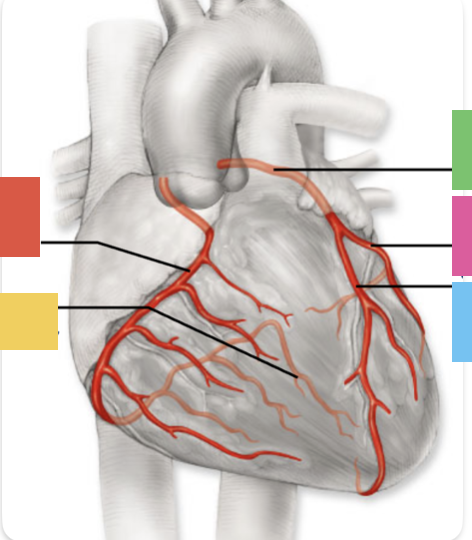

right coronary artery

posterior interventricular artery

left coronary artery

anterior interventricular artery

circumflex artery